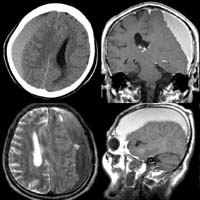

<ÇãÇ÷¼º

³úÁ¹Áß>

ÁÂÃø

Áß³úµ¿¸ÆÀÇ Æó»öÀ¸·Î ÀÎÇÑ ³ú°æ»ö¼Ò°ß(Ç÷°üÁ¶¿µ¼ú»ó

Áß³úµ¿¸ÆÀÌ º¸ÀÌÁö ¾Ê°í ÀÖ´Ù)

<°íÇ÷¾Ð¼º

³úÃâÇ÷>

<¼ö¼ú

Àü> <¼ö¼ú

ÈÄ>

¿ìÃø

Çǰ¢ºÎ ÃâÇ÷ȯÀÚÀÇ ³úCT¼Ò°ß(¼ö¼úÈÄ Ç÷Á¾ÀÌ

Á¦°ÅµÇ¾îÀÖ´Ù)

<³úÁöÁÖ¸·ÇÏÃâÇ÷>

Àü>

³úµ¿¸Æ·ù¿¡

ÀÇÇÑ ÁöÁÖ¸·ÇÏÃâÇ÷ÀÇ CT¼Ò°ß ¹× Ç÷°üÁ¶¿µ¼ú¿¡¼

Àü±³Å뵿¸Æ¿¡ µ¿¸Æ·ù°¡ º¸À̰í ÀÖ´Ù.

Àå¸é> <¼ö¼ú

¼ö¼ú

ÈÄ µ¿¸Æ·ù°¡ º¸ÀÌÁö ¾ÊÀ¸¸ç µ¿¸Æ·ù °æºÎ¿¡

Ŭ¸³ÀÌ µé¾î°¡ ÀÖ´Â °ÍÀÌ º¸À̰í

ÀÖ´Ù.

<³úÁ¤µ¿¸Æ±âÇü>

½Ã»óµ¿

ÀÎÁ¢ºÎ ºÎÀ§ÀÇ ³úÁ¤µ¿¸Æ±âÇüÀÇ MRI¿Í Ç÷°üÁ¶¿µ¼ú

¼Ò°ß